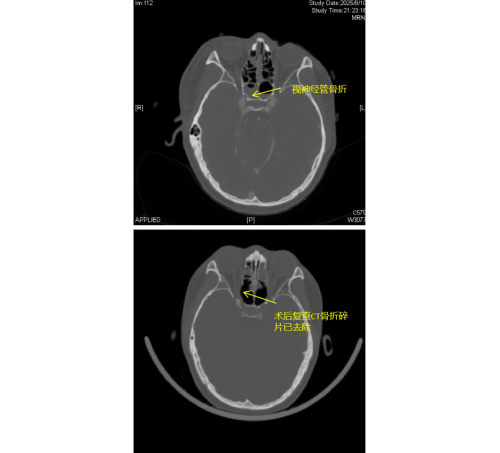

患者李琦(化名)是一名17岁少年,夜间骑电动车不慎撞上路边栏杆,随即出现右眼视力骤降、头痛头晕等症状,被120紧急送入立博体育|实时赛事直播与比分|权威专家分析与体育竞猜平台 急诊科。经检查发现,李琦存在颅底多处骨折、面颅多发骨折,尤其危急的是右侧视神经管骨折,碎裂的骨片直接压迫视神经及邻近的颈内动脉,导致右眼瞳孔散大、对光反射消失,视力完全丧失,病情极为危重。

由于视神经管周围解剖结构复杂,上方毗邻前颅底,下方紧邻颈内动脉和海绵窦,稍有不慎就可能导致脑脊液鼻漏、视神经断裂甚至颈内动脉破裂出血等严重后果,因此视神经的特殊位置被视为“手术雷区”。加之操作空间小,手术难度大,对于医生而言是一个巨大的挑战。视神经与鼻窦相邻,用鼻内镜经鼻窦进行视神经管减压手术,视野清楚、损伤最小。在手术过程中,康晓明医生利用高清鼻内镜,精准地清除了压迫视神经的骨折碎片,有效降低了神经压力。